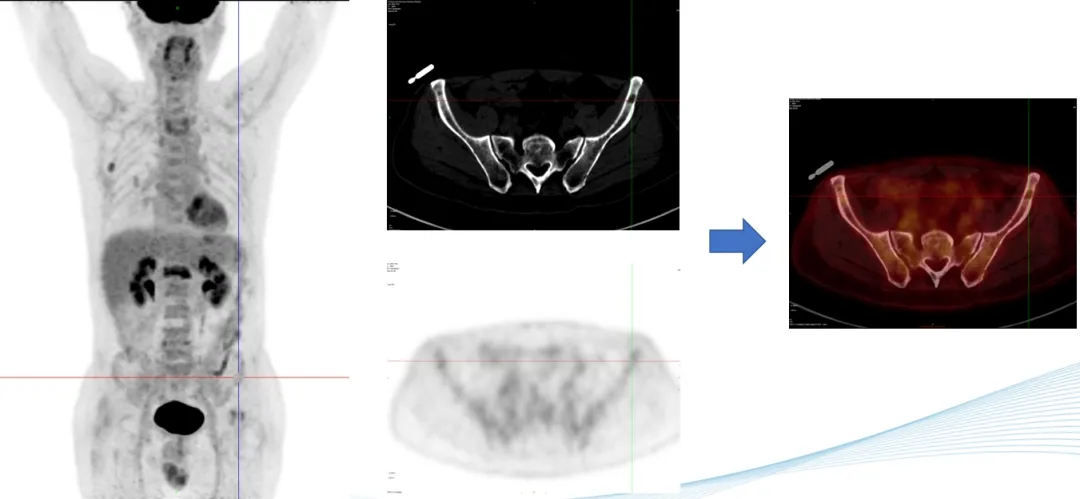

部分PET-CT影像图

前海人寿南宁医院核医学科PET-CT中心的阅片团队对扫描获得的李叔叔的全身影像图片反复多次的观察与比对,凭借着二十几年丰富的阅片经验,核医学科陈伟华主任发现,李叔叔肩胛骨、腰椎多处、双侧髂骨、左侧耻骨等出现了斑点片状、虫蚀样等形态溶骨性骨破坏,考虑恶性病变,多发性骨髓瘤可能性大,建议李叔叔立即进行骨髓穿刺检查。病理学检查结果证实了陈主任的影像诊断。腰痛的罪魁祸首终于找到,目前李叔叔已针对病因进行精准联合化疗。

多发性骨髓瘤(MM)是一种克隆性浆细胞异常增生的恶性疾病,多发于老年人,其发病率居恶性血液病的第二位,目前在我国其发病率呈逐年上升的趋势。PET-CT显像能够在分子水平上提供恶性肿瘤的增殖和代谢情况等信息,并可先于骨质结构变化,在早期发现骨髓的浸润和骨骼代谢的变化,这对于MM骨病的早期诊断具有重要意义。已有的研究结果表明,其在MM的诊断、分期、疗效监测和预后评估等方面具有重要意义。

18F-FDG是一种与葡萄糖结构相似的放射性核素标记化合物,其可进入细胞并滞留在细胞内。当葡萄糖代谢处于平衡状态时,18F-FDG在细胞内的滞留量与细胞消耗的葡萄糖量大体一致,通过18F示踪可反映机体器官、组织和细胞的葡萄糖分布和摄取水平。MM的骨骼和髓外浸润病灶具有高代谢的特点,故在18F-FDG PET-CT显像中显示为高摄取。

PET-CT显像不仅能够直观地显示出MM病灶的代谢情况,而且通过一次检查即可评价全身脏器和骨骼有无浸润,从而多方位、全方面地显示病灶的部位和数量。因此,其对于MM的诊断,特别是对于存在髓外器官受累的患者具有独特的优势。